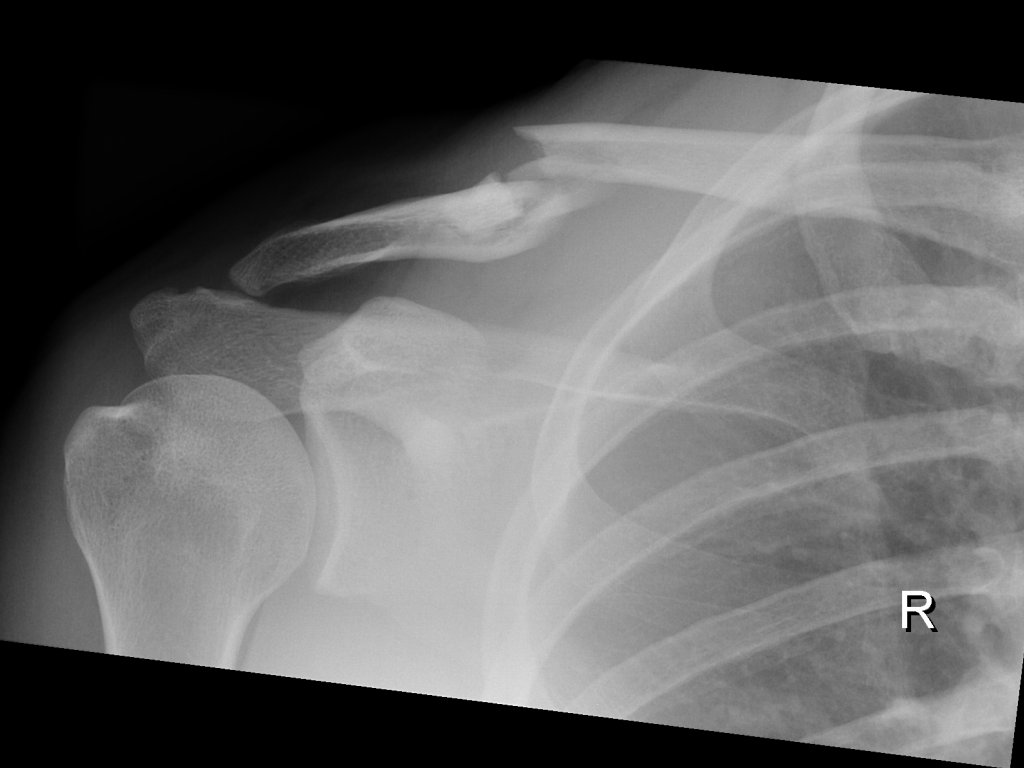

Clavicula-Fraktur (23./25. Juli/2. August 2007)